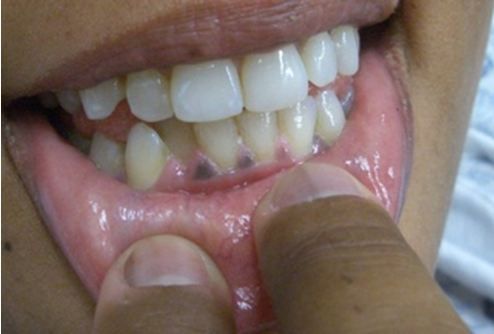

Fig 2. Gum hyperpigmentation in Addison's disease.

Although there are many conditions that can cause nausea and abdominal pain, there are few conditions that cause global hyperpigmentation. The combination is most consistent with primary adrenal insufficiency (Addison’s disease). At right, Figure 2 shows gum hyperpigmentation and Figure 3 highlighs palmar crease hyperpigmentation (author’s hand shown on the left for comparison; click on images to enlarge).

Primary adrenal insufficiency or Addison’s disease, is the result of destruction of the adrenal cortex. It is less common than secondary adrenal insufficiency but more severe and pronounced because mineralocorticoids are also affected, causing dehydration and electrolyte abnormalities. In addition, feedback mechanisms result in increased pituitary production of ACTH in Addison's disease. ACTH also stimulates melanocytes, leading to the signature hyperpigmentation that affects not only sun-exposed skin but also the palms and even the gums (Figures 2 and 3). Symptoms are otherwise similar to secondary adrenal insufficiency but are often more pronounced with more hypotension. Initial treatment is similar, including IV fluids, supportive care and steroid replacement. Long term both glucocorticoids and mineralocorticoids will require replacement.